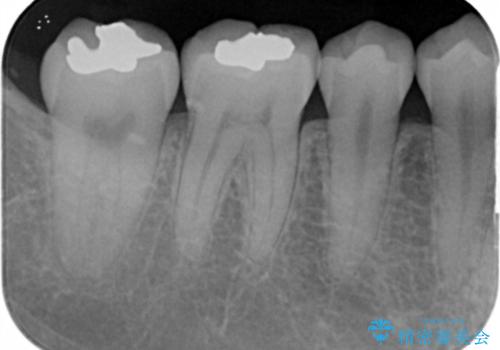

- 奥歯に以前プラスチックの樹脂で虫歯治療を行った患者様です。

歯と樹脂の隙間が黒くなってきていて若干虫歯になっていました。

樹脂は長期的な予後が悪いため、樹脂を外してゴールドインレーに置き換えました。

樹脂下の虫歯は除去しています。

今回は、虫歯が進行したというよりは予防的な意味も含めて、金属で丈夫な適合の良いゴールドインレー(PGAインレー)による修復治療を行うことにしました。

- ゴールドインレー6万円 ×2本費用は治療当時の料金となります